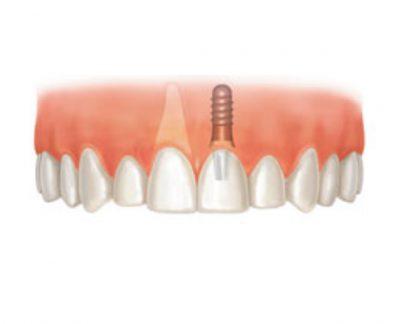

Comparable à une racine artificielle, l’implant dentaire est un petit objet cylindrique de la forme d’une vis qu’un chirurgien-dentiste fixe dans l’os maxillaire du patient. Deux a trois mois sont nécessaires à son intégration osseuse. Il remplace la racine de la dent perdue qui offre ainsi une base robuste pour accueillir une couronne, un bridge ou une prothèse dentaire amovible, et permettre au patient de mastiquer normalement et sans encombres.